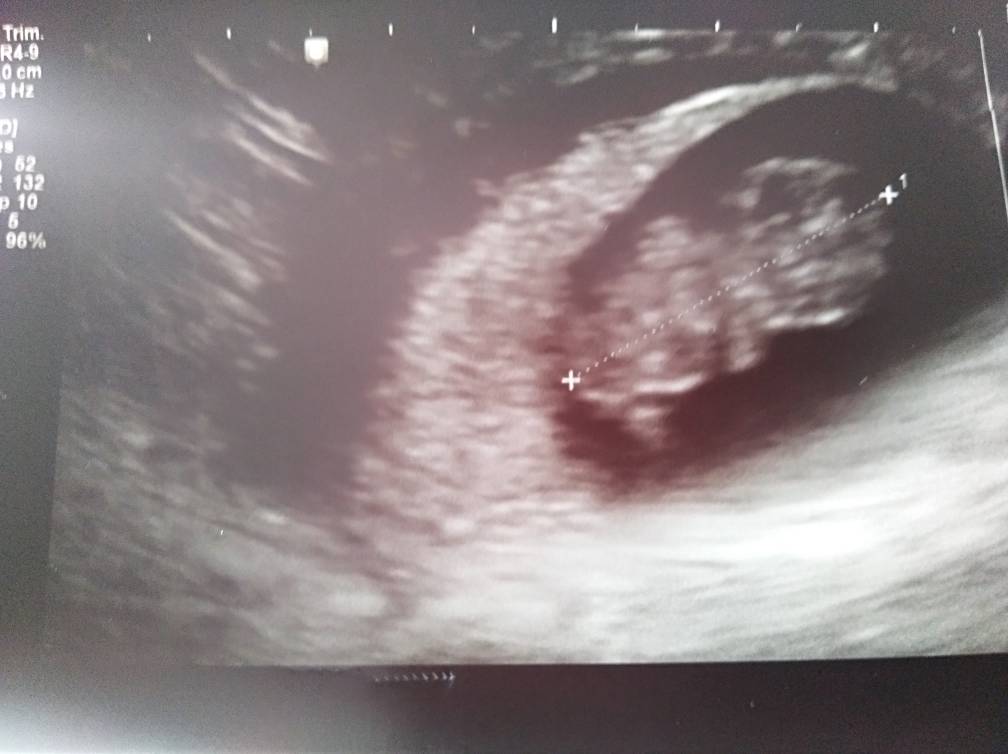

Dziewczyny już po wizycie. Jest serduszko pięknie bijące [emoji7] Z usg dzidziol większy o 3 dni czyli 8+6 wychodzi.

Ale ulga bo miałam stresa na maxa a wizyta o pół godziny sie jeszcze przesunela.

IMG_20190329_132438.jpeg